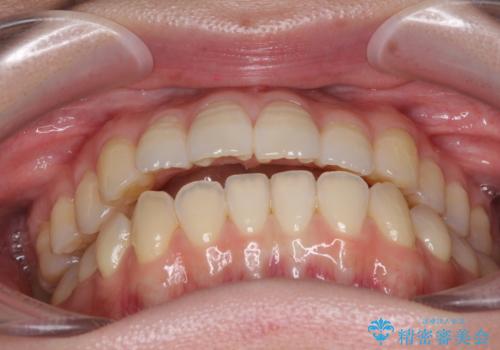

オープンバイトのインビザラインを用いた再矯正

- 矯正治療の後戻りを気にして来院された患者様です。

オープンバイト(前歯の開咬)と下顎骨の偏位による不正咬合が認められました。

骨格の偏位による不正咬合は改善しきれないことを理解いただいた上で、インビザラインにて矯正治療を行うこととしました。

オープンバイトは後戻りを起こしやすいため、極力そのリスクを軽減するため、奥歯を圧下させるように治療を進めていきました。

下顎骨の偏位が顕著であったため、上下の正中を合わせることはできませんでしたが、患者様には大変満足していただきました。